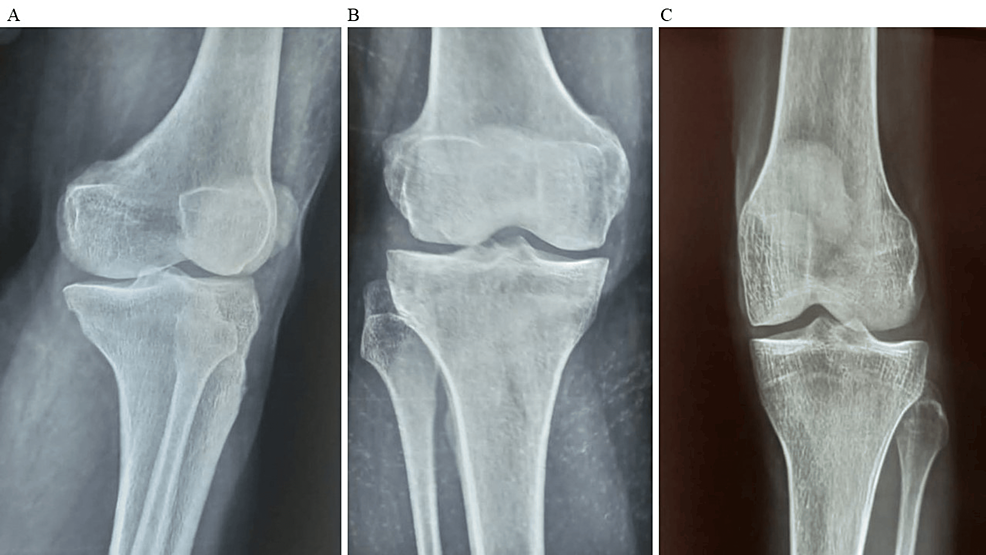

平均WOMAC評分從基線時的56.8±11.5下降到六個月時的41.2±10.6。此外,還監測了不良事件的發生情況,報告了七起不良事件,占參與者的28.0%。這些發現強調了該治療在六個月內減輕疼痛和改善功能結果方面的有效性。下圖2顯示了開始干細胞治療后骨骼的側視圖和前后視圖。?